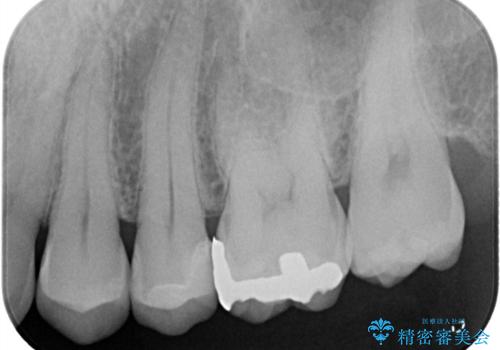

【セラミックインレー】他院で詰めた銀歯がフロスをしたら取れた!

- 「フロスをしたら銀歯が取れた」を主訴に来院された患者様です。

レントゲン検査で虫歯が認められました。

セラミックインレーで治療を行いました。

古い材料を除去後、その下に大きな虫歯が広がっていました。

神経の近くまで虫歯が広がっていたため、虫歯の除去後、神経を保護する材料をおきセラミックインレーで治療を行いました。